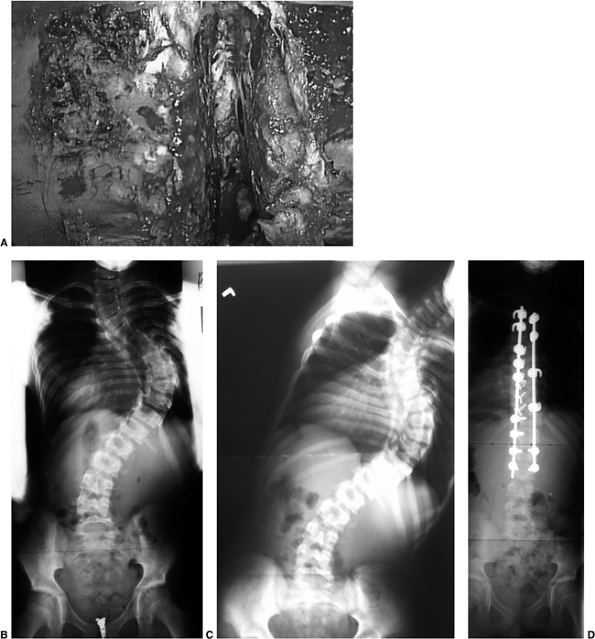

by looking for soft tissue abnormalities, congenital bony abnormalities

hemivertebrae (Fig. 18.13) and bar formation